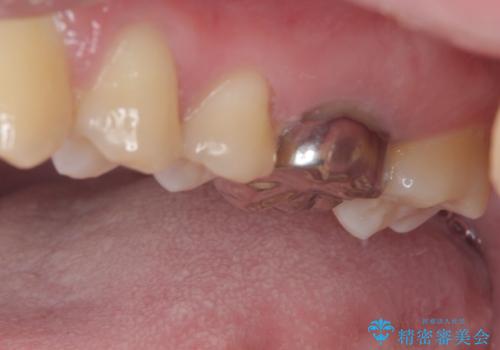

右下の銀の詰め物は、外してむし歯を除去した後、セラミックインレーにて修復することとしました。

左上の銀歯は、銀歯の下に金属の土台が入っているため、その土台を除去し、ファイバーコアにやり替えて、オールセラミッククラウンにて補綴することとしました。